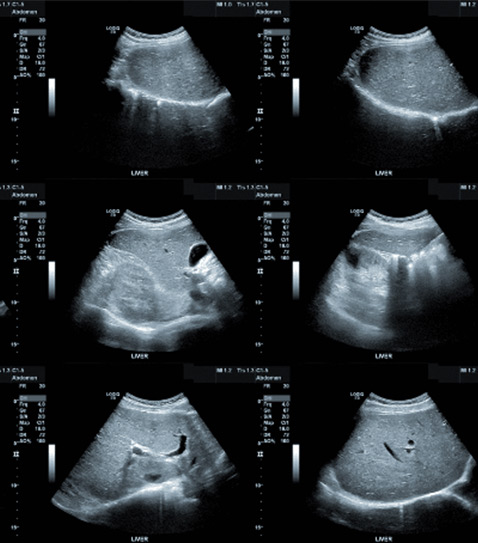

Abdominal

Es una prueba que se utiliza para examinar los órganos internos del abdomen, como hígado, bazo, vesícula biliar, páncreas, riñones y la aorta abdominal.

Hepática y vías biliares

El objetivo es visualizar el estado del hígado, vesícula biliar, páncreas y los conductos cístico y colédoco; esta ecografía puede diagnosticar enfermedades como, adenomas, quistes, tumores del páncreas, pancreatitis, cálculos y tumores de la vesícula y vías biliares, colecistitis, entre otras.